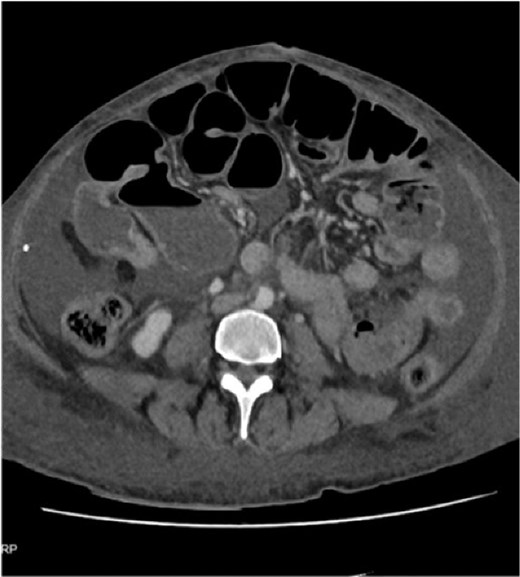

Three months later, she was admitted with anaemia(Hb:6 g/dL), profound hypoalbuminemia (albumin:15 g/L) and generalized oedema. Computed tomography (CT) showed dilated SI loops with a possible transition point in the right mid-abdomen in keeping with a multifocal mechanical bowel obstruction (Fig. 1).